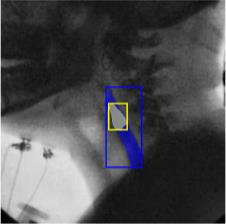

The videofluoroscopic swallowing study (VFSS) is a gold-standard imaging technique for assessing swallowing, but analysis and rating of VFSS recordings is time consuming and requires specialized training and expertise. Researchers have recently demonstrated that it is possible to automatically detect the pharyngeal phase of swallowing and to localize the bolus in VFSS recordings via computer vision, fostering the development of novel techniques for automatic VFSS analysis. However, training of algorithms to perform these tasks requires large amounts of annotated data that are seldom available. We demonstrate that the challenges of pharyngeal phase detection and bolus localization can be solved together using a single approach. We propose a deep-learning framework that jointly tackles pharyngeal phase detection and bolus localization in a weakly-supervised manner, requiring only the initial and final frames of the pharyngeal phase as ground truth annotations for the training. Our approach stems from the observation that bolus presence in the pharynx is the most prominent visual feature upon which to infer whether individual VFSS frames belong to the pharyngeal phase. We conducted extensive experiments with multiple convolutional neural networks (CNNs) on a dataset of 1245 bolus-level clips from 59 healthy subjects. We demonstrated that the pharyngeal phase can be detected with an F1-score higher than 0.9. Moreover, by processing the class activation maps of the CNNs, we were able to localize the bolus with promising results, obtaining correlations with ground truth trajectories higher than 0.9, without any manual annotations of bolus location used for training purposes. Once validated on a larger sample of participants with swallowing disorders, our framework will pave the way for the development of intelligent tools for VFSS analysis to support clinicians in swallowing assessment.